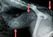

Katze mit Nadel in der Speiseröhre